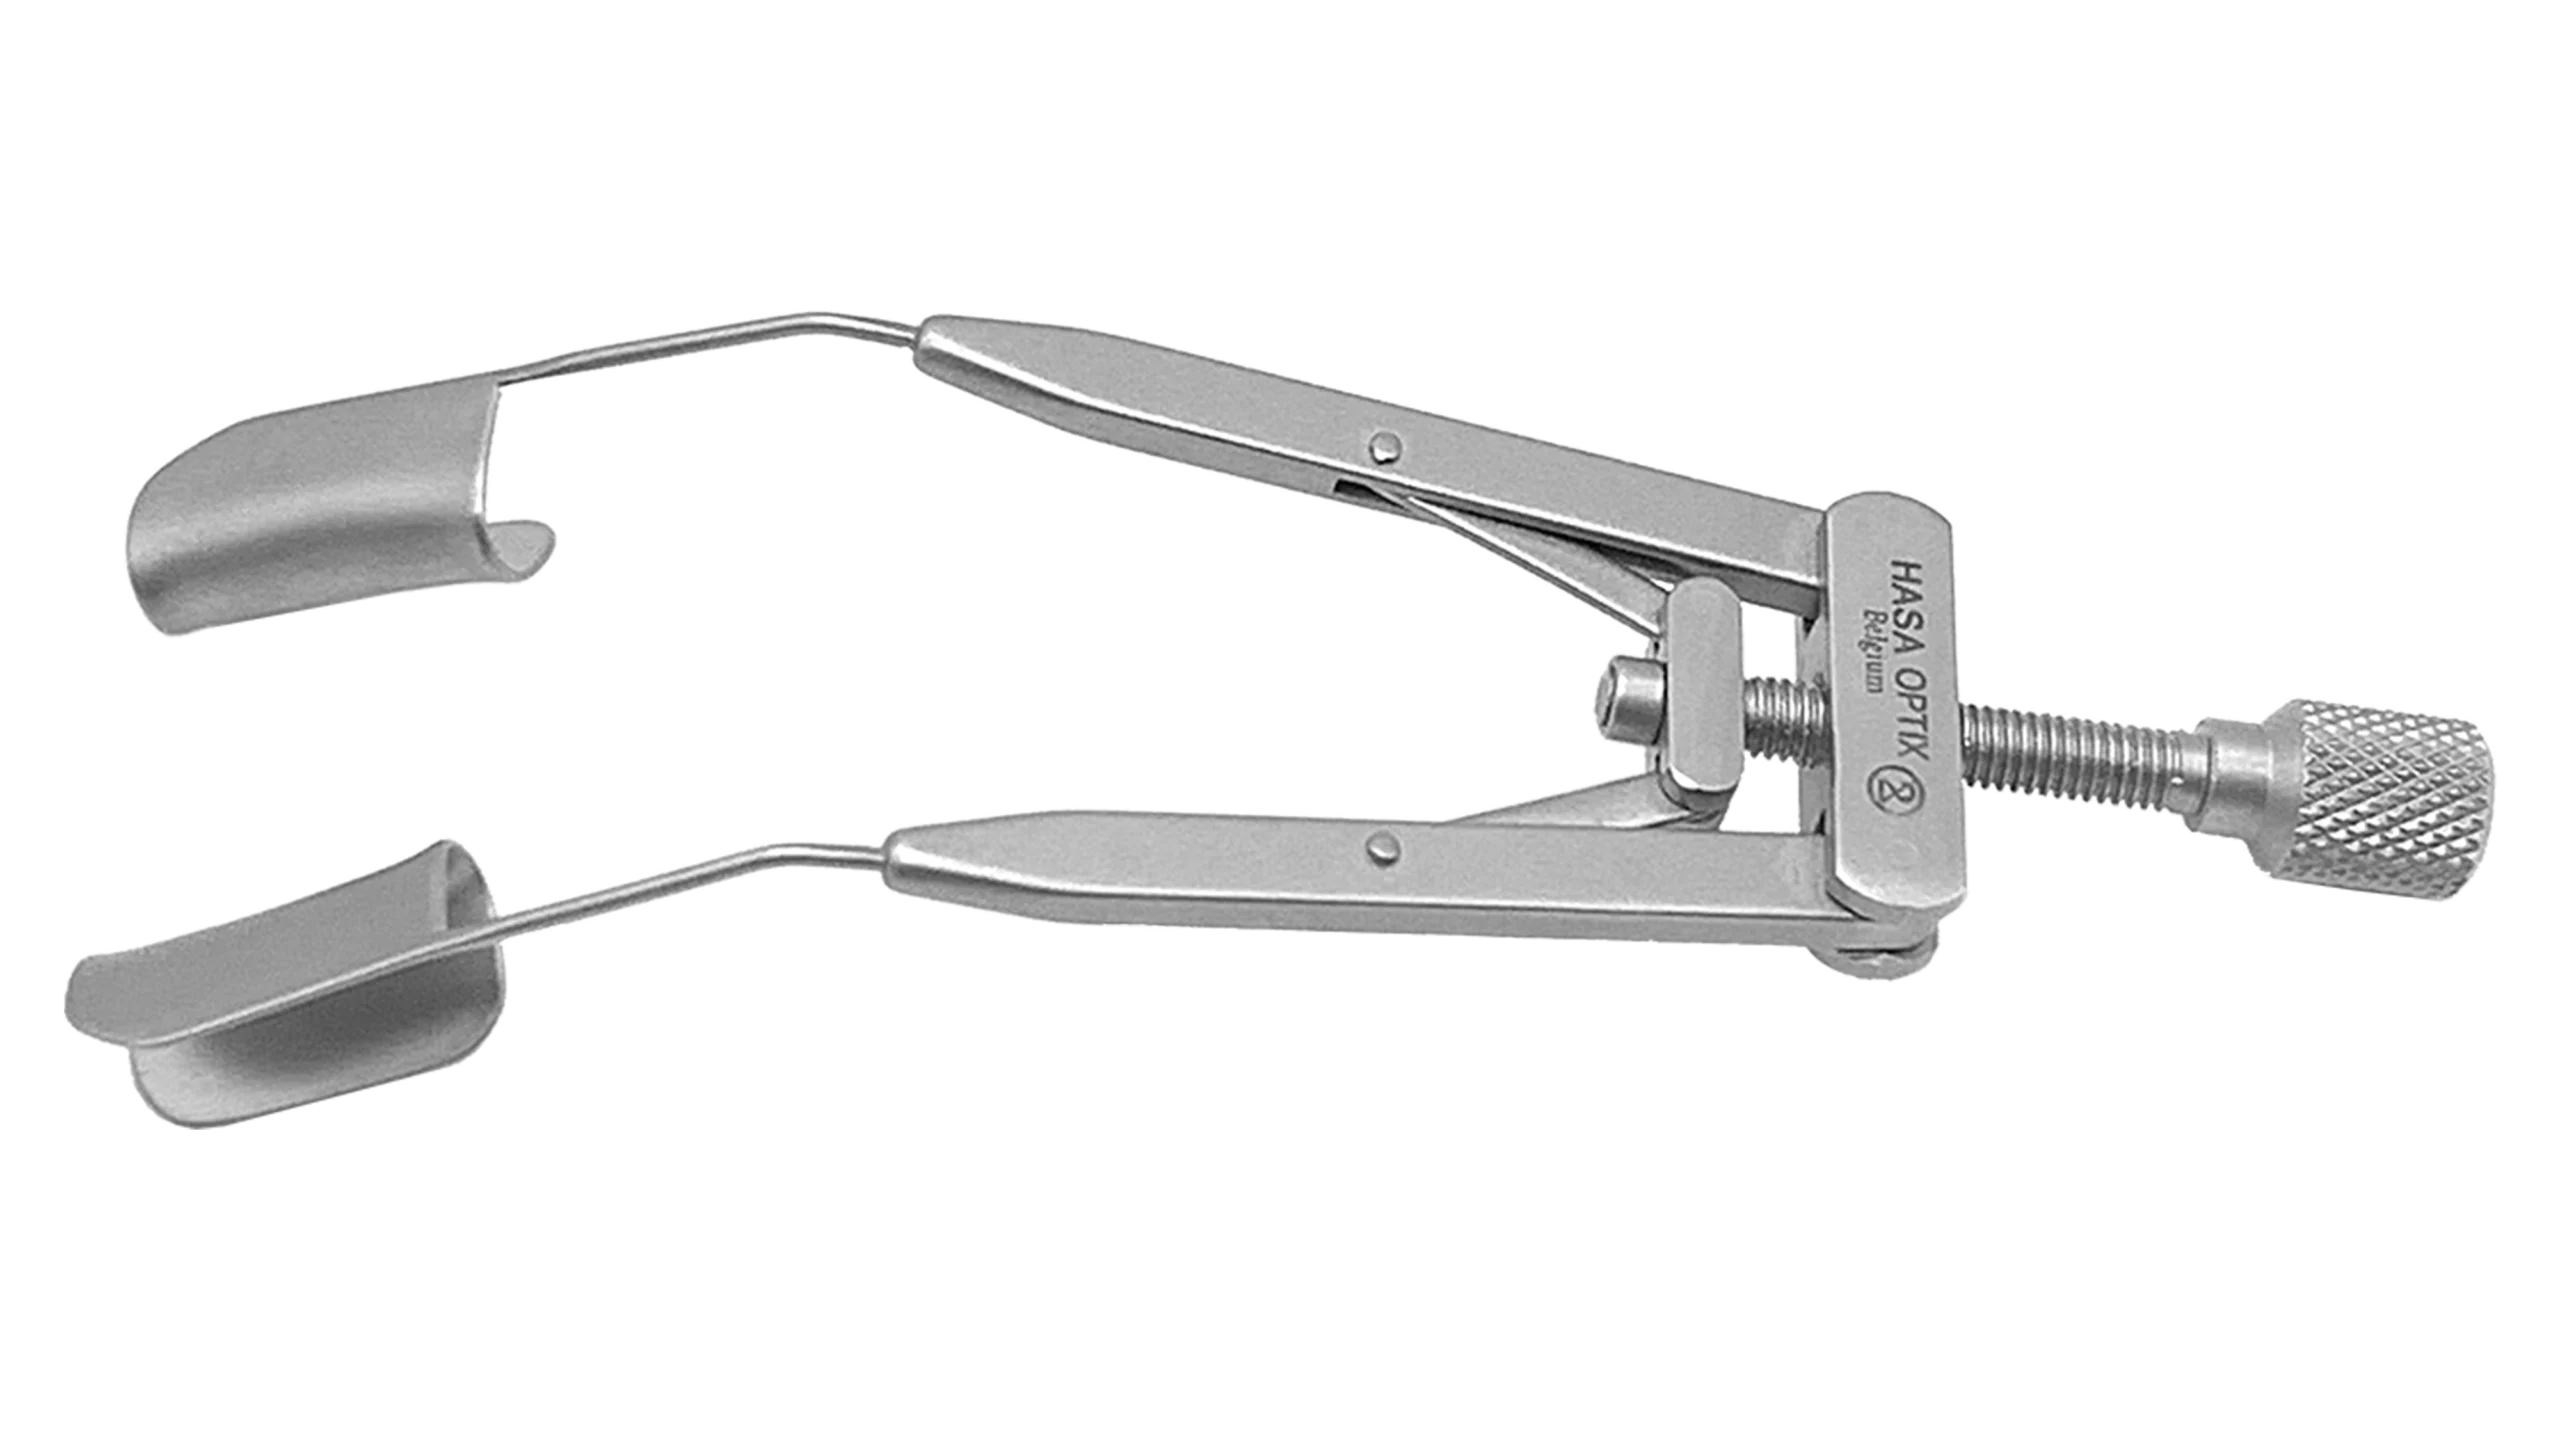

Ophthalmic Surgical Instruments

Wide range of recyclable ophthalmic surgery instruments.